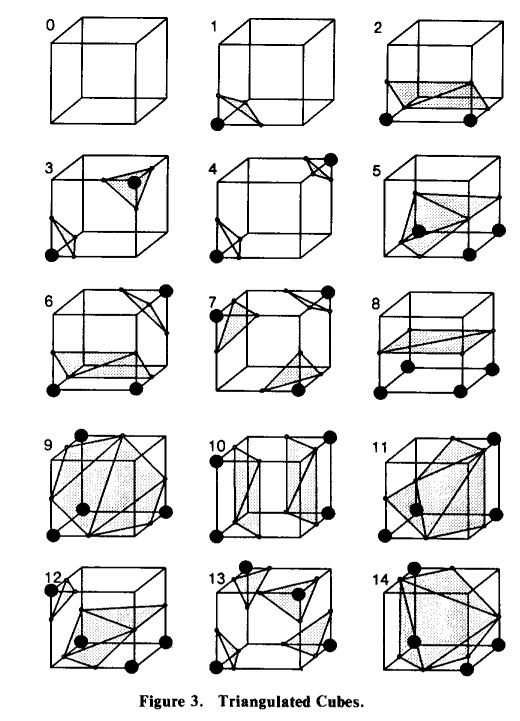

为了针对某个小立方体去生成局部三角形,MarchingCubes非常丧心病狂地做了一件事:穷举了256种情况能生成的三角形。(虽然,这256种情况可以被概括成15个基本情况,基本情况经过旋转、镜像等操作可以生成所有的256种情况)。

上图就是引用自1987年论文[1]里面的图,图里描述了15种基本情况。上图基本说说明了,什么情况就可以在哪生成三角形。其中三角形的每个顶点都是在小立方体的棱上的。于是每个小立方体都这么干,所有小立方体生成的三角形拼在一起就是目标器官的表面了。